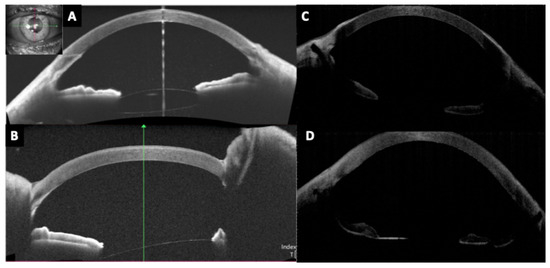

Background and Objectives: Optic disc drusen (ODD) can mimic papilledema and are linked to structural crowding, microvascular change, and visual-field loss. We synthesized structural/microvascular differences, functional status and change, diagnostic...